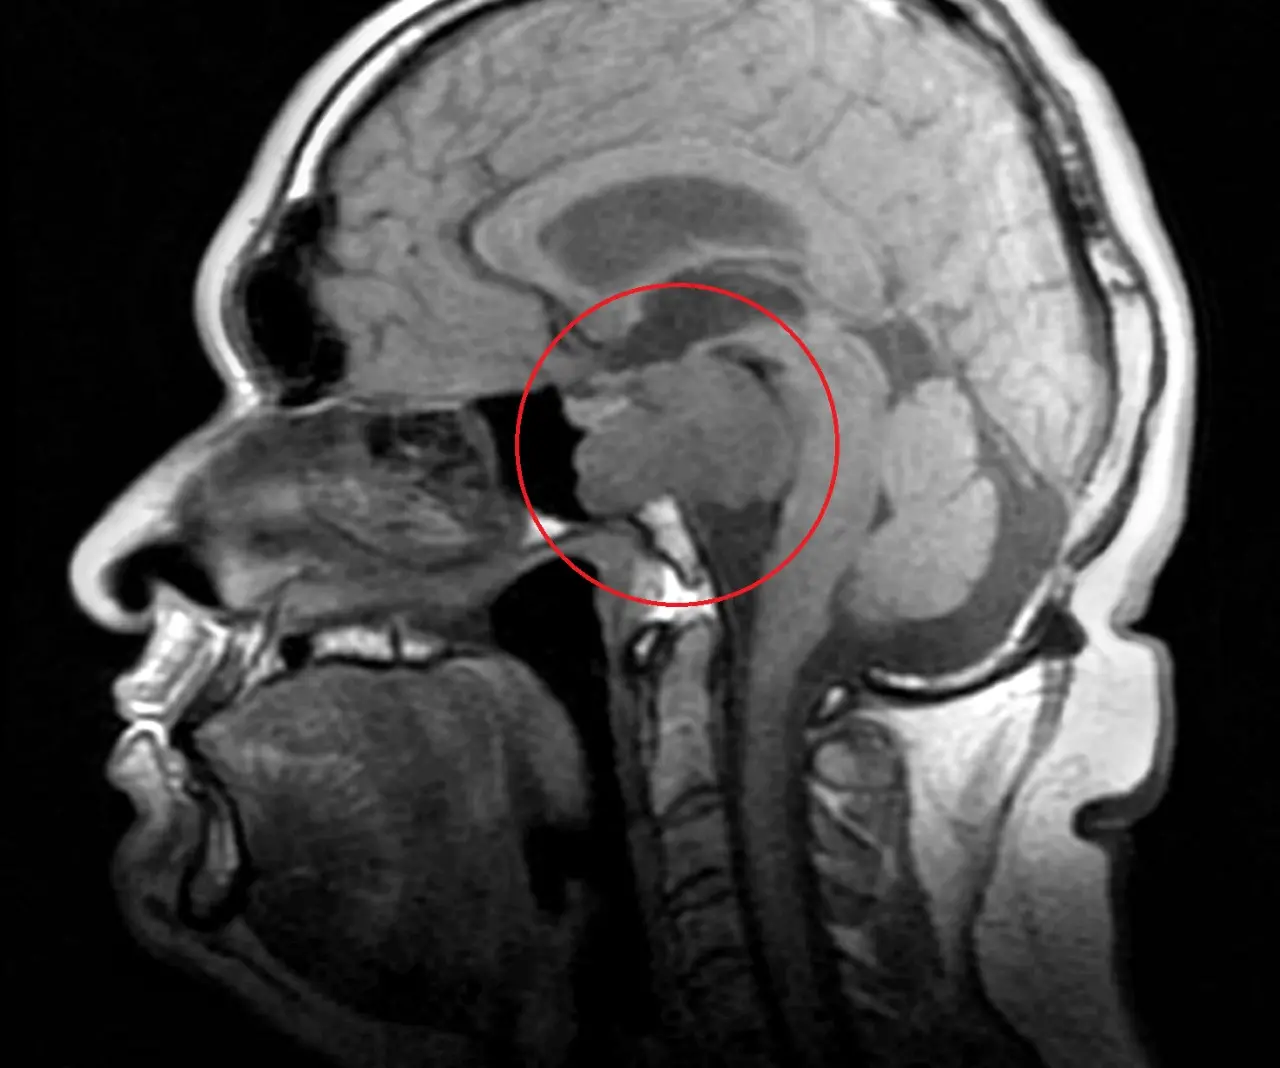

Legenda: Por ser uma doença rara, médicos ainda não sabem precisar a data de surgimento do tumor, podendo ter se desenvolvido desde a infância de Eberth

Foto: Arquivo pessoal

No entanto, por estar localizado em uma área delicada do cérebro, entre o tronco cerebral e a córnea, e ter o tamanho de um limão, os médicos só poderão retirar parte do tumor. O restante deverá ser tratado com a protonterapia, procedimento que garante cerca de 80% a 90% de cura.

Por isso, voltou em maio novamente. Depois de um outro neurologista passar uma ressonância, constataram o tumor. “O médico olhou, mostrou para outro, olhou de novo e disse que eu estava com um câncer seríssimo no cérebro”.

Conforme o médico Francisco Caubi Ferreira, Residente Sênior de Neurocirurgia do Hospital Geral de Fortaleza (HGF), a região em que o tumor está localizado apresenta nervos essenciais para a rotina diária do paciente, como locomoção, fala, deglutição e até respiração.

Por conta da complexidade do local, há um alto risco em aplicar procedimentos como a radioterapia ou mesmo a radiocirurgia, já que não apresentam tanta precisão como a protonterapia.

A proximidade do tumor com estruturas nervosas importantes, como nervos cranianos e centro respiratório e da deglutição, torna essa opção também repleta de risco de sequelas graves.

Francisco Caubi Ferreira

Assim, Eberth pode ter sequelas na visão, na coordenação motora e até a perda de memória. Por isso, dentre as opções, a irradiação por feixe de prótons se configura como a melhor alternativa, “pois é mais precisa em lesionar apenas a área tumoral, amenizando os danos neurológicos subsequentes”, detalha o Dr.Caubi.